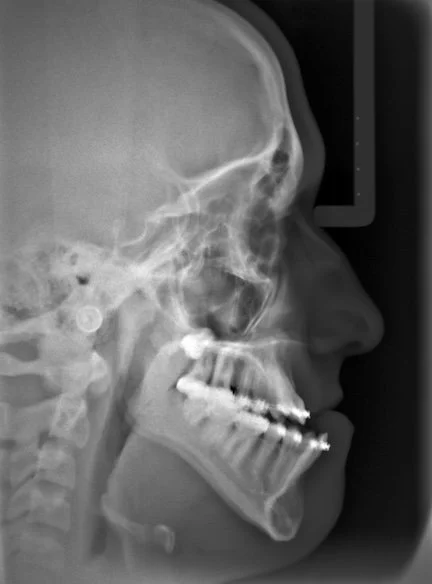

Lateral X-ray of a person's skull showing facial bones, jaw, and teeth.

The orthodontist's role comes first. Before any surgery takes place, metal or clear braces to align the teeth and position each arch — upper and lower — so that the teeth are properly situated over their respective jaw. This is counterintuitive to many patients, because the bite may actually look worse before surgery than it did at the start. That's by design. We are setting up each jaw independently so that when the surgeon moves them into their correct relationship, the teeth will meet properly.

The surgeon's role is to then reposition the jaws with precision — moving them into the relationship that orthodontics alone cannot achieve. This is highly planned, carefully timed, and coordinated closely between our office and the surgical team at every step.

After surgery, orthodontic treatment continues to refine and finish the result. For most patients, the goal is to have braces off within four to six months of surgery — a timeline that feels manageable once the hardest part is behind them.